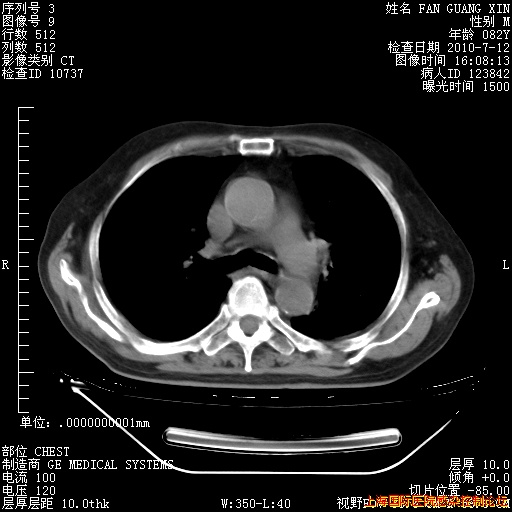

6月12日纵膈窗